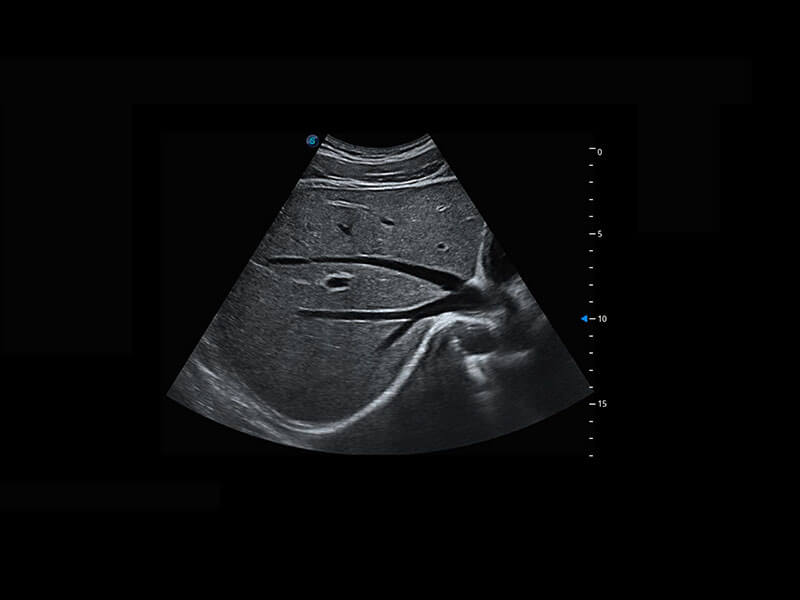

生殖健康

P60优异的图像质量搭载专科探头,在妇科基础疾病的诊断、卵泡生长的监测、输卵管通畅情况的判别等方面为您提供生殖应用方案。

• 腔内妇科-宫腔分离

• 腔内妇科-卵巢